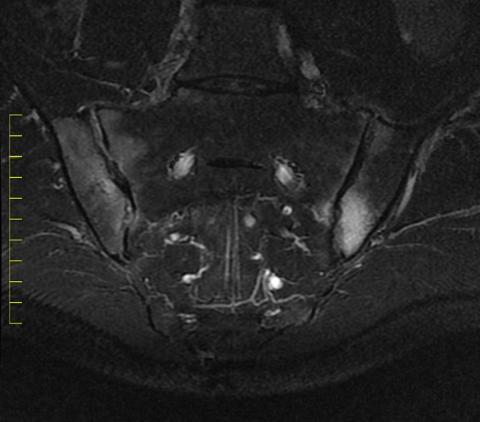

MR-billede af bækken og nedre ryghvirvler. Betændelsen lyser op og er derfor nem at se.

Foto: Mikkel Østergaard